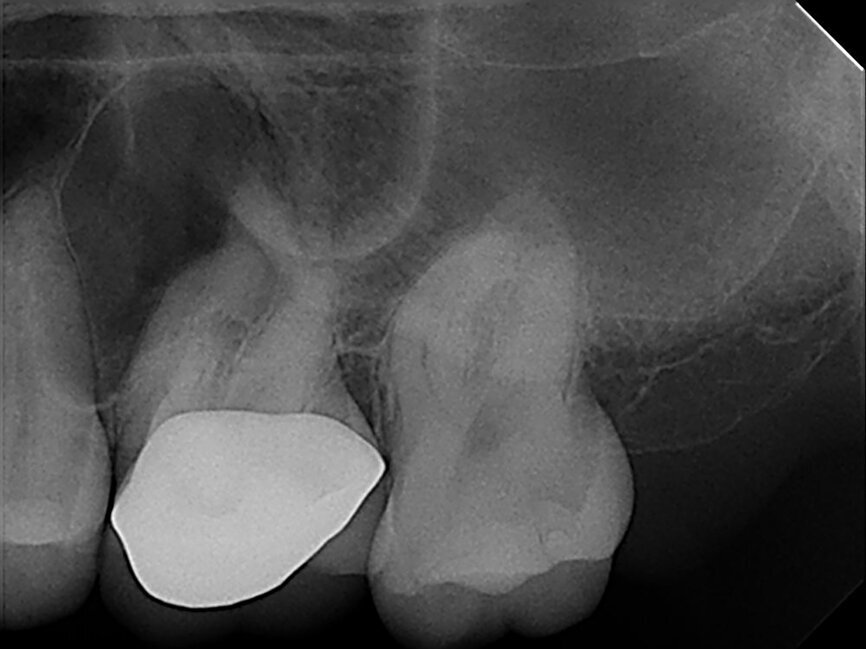

A 33-year-old patient with irreversible pulpitis and symptomatic periapical periodontitis affecting tooth #26. (Image: Dr Yanina Figueroa)

In this article, I report a case of a 33-year-old patient with irreversible pulpitis and symptomatic periapical periodontitis affecting tooth #26 (Fig. 1). This case was diagnosed and accessed through the crown using diamond burs and then irrigated with sodium hypochlorite.